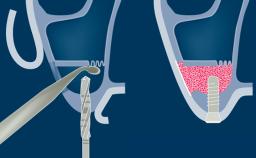

Sinus floor elevation using either the lateral window or transcrestal approach is a predictable surgical procedure with proven success, low complication rates, and high survival rates.

This learning module will provide an overview of the most commonly seen intraoperative and postoperative complications associated with sinus floor elevation and will discuss management in terms of preventative measures as well as treatment strategies.

- intraoperative complications of lateral window sinus floor elevation

- postoperative complications of sinus floor elevation